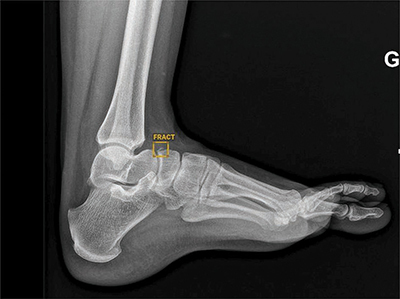

Objectives: The aims of this study were: (a) to evaluate the performance of an artificial intelligence (AI) software package (Boneview Trauma, Gleamer) for the detection of post-traumatic bone fractures in radiography as a standalone; (b) used by two radiologists (osteoarticular senior and junior); and (c) to determine to whom AI would be most helpful.

Materials and methods: Within 14 days of a trauma, 101 consecutive patients underwent radiographic examination of the upper or lower limbs. The definite diagnosis for identifying fractures was: (a) radio-clinical consensus between the radiologist on-call who analyzed the images and the orthopedist (Group 1); (b) Cone Beam computed tomography (CBCT) exploration of the area of interest, in case of doubts or absence of consensus (Group 2). Independently of this diagnosis for both groups, the radiographic images were separately analyzed by two radiologists (osteoarticular senior: SR; junior: JR) prior without, and thereafter with the results of AI.

Results: AI performed better than the radiologists in detecting common fractures (Group 1), but not subtle fractures (Group 2). In association with AI, both radiologists increased their overall performances in both groups, whereas this increase was significantly higher for the JR (p < 0.05).

Conclusion: AI is reliable for common radiographic fracture identification and is a useful learning tool for radiologists in training. However, the software's overall performance does not exceed that of an osteoarticular senior radiologist, particularly in case of subtle lesions.